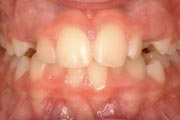

Crowding

Before